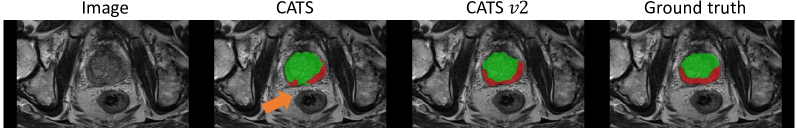

We compared the nnUnet [32], TransFuse [19] and CATS [20] to our proposed method for the prostate segmentation task in Tab. 3. CATS v2 has the highest Dice scores on all labels, i.e., both the peripheral zone (PZ) and the transition zone (TZ). This dataset was chosen because of the inherent challenge in segmenting two closely adjoined regions that exhibit considerable inter-subject variability. The qualitative improvements between original CATS and CATS v2 are shown in Fig. 4. A more robust segmentation is produced by the proposed method by correcting the false positives.